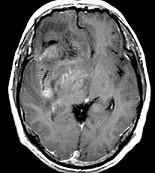

问题 男,55岁,头胀感1年余,头痛3日,请根据所提供图像,选择最可能的诊断()

选项 A.(右额颞)病毒性脑炎 B.(右额颞)星形细胞瘤 C.(右额颞)淋巴瘤 D.(右额颞)少突胶质细胞瘤 E.(右额颞)胶质母细胞瘤

答案 D